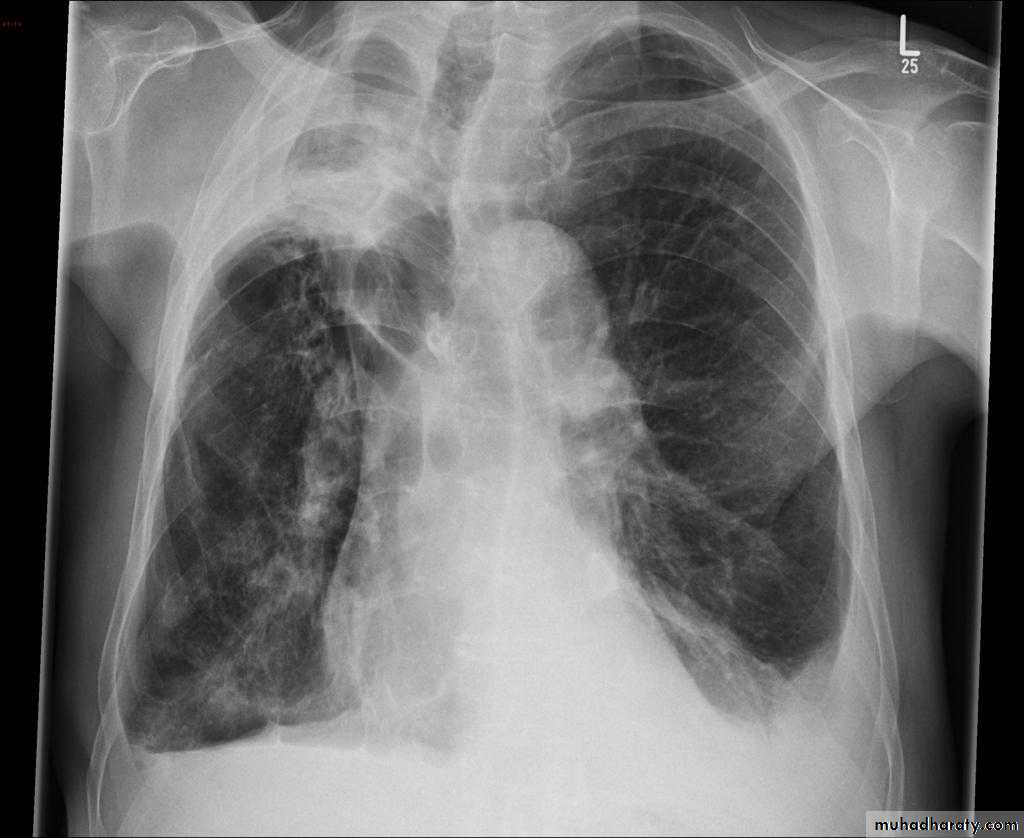

Plain radiograph

Chest x-rays are usually abnormal1. Tram-track opacities are seen in cylindrical bronchiectasis, and

2. air-fluid levels may be seen in cystic bronchiectasis.

Honey comb shadow

3.Overall there appears to be an increase in bronchovascular markings, and bronchi seen end on may appear as ring shadows .

4.Pulmonary vasculature appears ill-defined, thought to represent peri bronchovascular fibrosis .